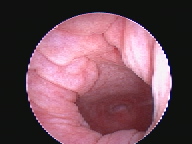

Endoscopia Rígida

A Clínica Veterinária de Albufeira já disponibiliza serviços de minima invasão como solução alternativa às cirurgias tradicionais, sejam estas profiláticas (como as ovariohisterectomias, orquiectomia de criptorquideos) ou de diagnóstico (biópsia, cistotomias, etc). A mais valia desta técnica é a utilização de orifícios naturais ou incisões minímas para aceder ao sistema desejado ( urinário, respiratório, digestivo, reprodutivo), sendo a recuperação mais rápida e a dor pós operatória muito menor.